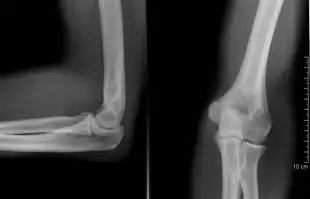

The elbow is the region between the upper arm and the forearm that surrounds the elbow joint.[1] The elbow includes prominent landmarks such as the olecranon, the cubital fossa (also called the chelidon, or the elbow pit), and the lateral and the medial epicondyles of the humerus. The elbow joint is a hinge joint between the arm and the forearm;[2] more specifically between the humerus in the upper arm and the radius and ulna in the forearm which allows the forearm and hand to be moved towards and away from the body.[3][4] The term elbow is specifically used for humans and other primates, and in other vertebrates forelimb plus joint is used.[1]

When in anatomical position there are four main bony landmarks of the elbow. At the lower part of the humerus are the medial and lateral epicondyles, on the side closest to the body (medial) and on the side away from the body (lateral) surfaces. The third landmark is the olecranon found at the head of the ulna. These lie on a horizontal line called the Hueter line. When the elbow is flexed, they form a triangle called the Hueter triangle, which resembles an equilateral triangle.[5]

Right: AP X ray of a dislocated right elbow

Fractures

There are three bones at the elbow joint, and any combination of these bones may be involved in a fracture of the elbow. Patients who are able to fully extend their arm at the elbow are unlikely to have a fracture (98% certainty) and an X-ray is not required as long as an olecranon fracture is ruled out.[27] Acute fractures may not be easily visible on X-ray.[28]

Dislocation

Elbow dislocations constitute 10% to 25% of all injuries to the elbow. The elbow is one of the most commonly dislocated joints in the body, with an average annual incidence of acute dislocation of 6 per 100,000 persons.[30] Among injuries to the upper extremity, dislocation of the elbow is second only to a dislocated shoulder. A full dislocation of the elbow will require expert medical attention to re-align, and recovery can take approximately 8–14 weeks.